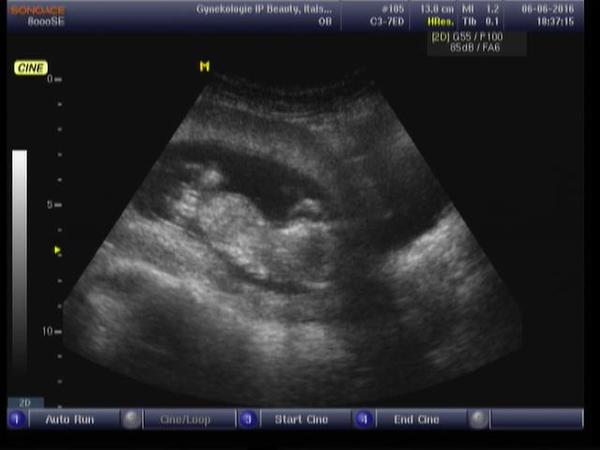

Je to holčička nebo chlapeček? Foto ultrazvuku

Ahoj maminky a budoucí maminky 😉 Prosím, poradila byste mi některá, co vidíte na fotce z ultrazvuku ve 20. týdnu za pohlaví? Určitě jste foteček viděly už mraky, proto vás žádám o radu...Nechci nikoho ovlivnit, proto svůj tip řeknu později 🙂 Děkuju moc!!!